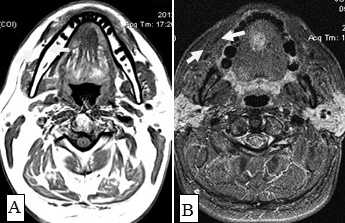

Рис.1. Пациент Ж., 58 лет. МСКТ ротоглотки в аксиальной проекции: А - нативное исследование, В - с внутривенным болюсным контрастированием. Небольшая инфильтративная опухоль ротоглотки (левой небной миндалины Т1 стадии). Границы опухоли не дифференцируются, накопление контраста слабое (показатели плотности в нативной фазе исследования 45 ед.Н, после внутривенного болюсного усиления - 56 ед.Н). Определяется смещение левой стенки ротоглотки, сглаженность контура (стрелки)

Сложно было выявлять опухоли малых размеров (Т1,Т2 стадии), расположенные в передних отделах дна полости рта из-за расположенных рядом костных тканей, зубов, наличия пломбировочного материала вследствие выраженных артефактов от плотных структур. В ряде случаев визуализацию облегчало наличие язвенного дефекта в структуре опухоли (рис. 5). При всех опухолях Т3, Т4 стадии определялось повышение плотности после введения контрастного вещества, их края четко визуализировались относительно окружающих тканей. Во всех случаях Т3, Т4 стадии удавалось определить размер опухоли и оценить инфильтрацию и распространение в соседние зоны, а также за среднюю линию (рис. 6).

Большинство пораженных метастазами лимфатических узлов имели размеры более 1,0 см, округлую форму (рис. 12). Внутривенное контрастирование при оценке изменений в лимфатическом узле являлось обязательным условием для уточнения внутренней структуры и выявления зон некроза. В результате гипоксии и распада ткани формируется центральная зона некроза, не накапливающая контрастный препарат при внутривенном болюсном усилении. При этом отмечается повышение плотности в периферических отделах лимфатического узла (рис. 13).

Рис. 13. Пациентка К.,64 года. МСКТ ротоглотки, шеи в аксиальной проекции с внутривенным болюсным контрастированием. Рак языка с метастазами в лимфатические узлы средней яремной группы. Отмечается контрастирование пораженных лимфатических узлов по периферии, низкой плотности центральная зона некроза (стрелки). Билатеральное поражение